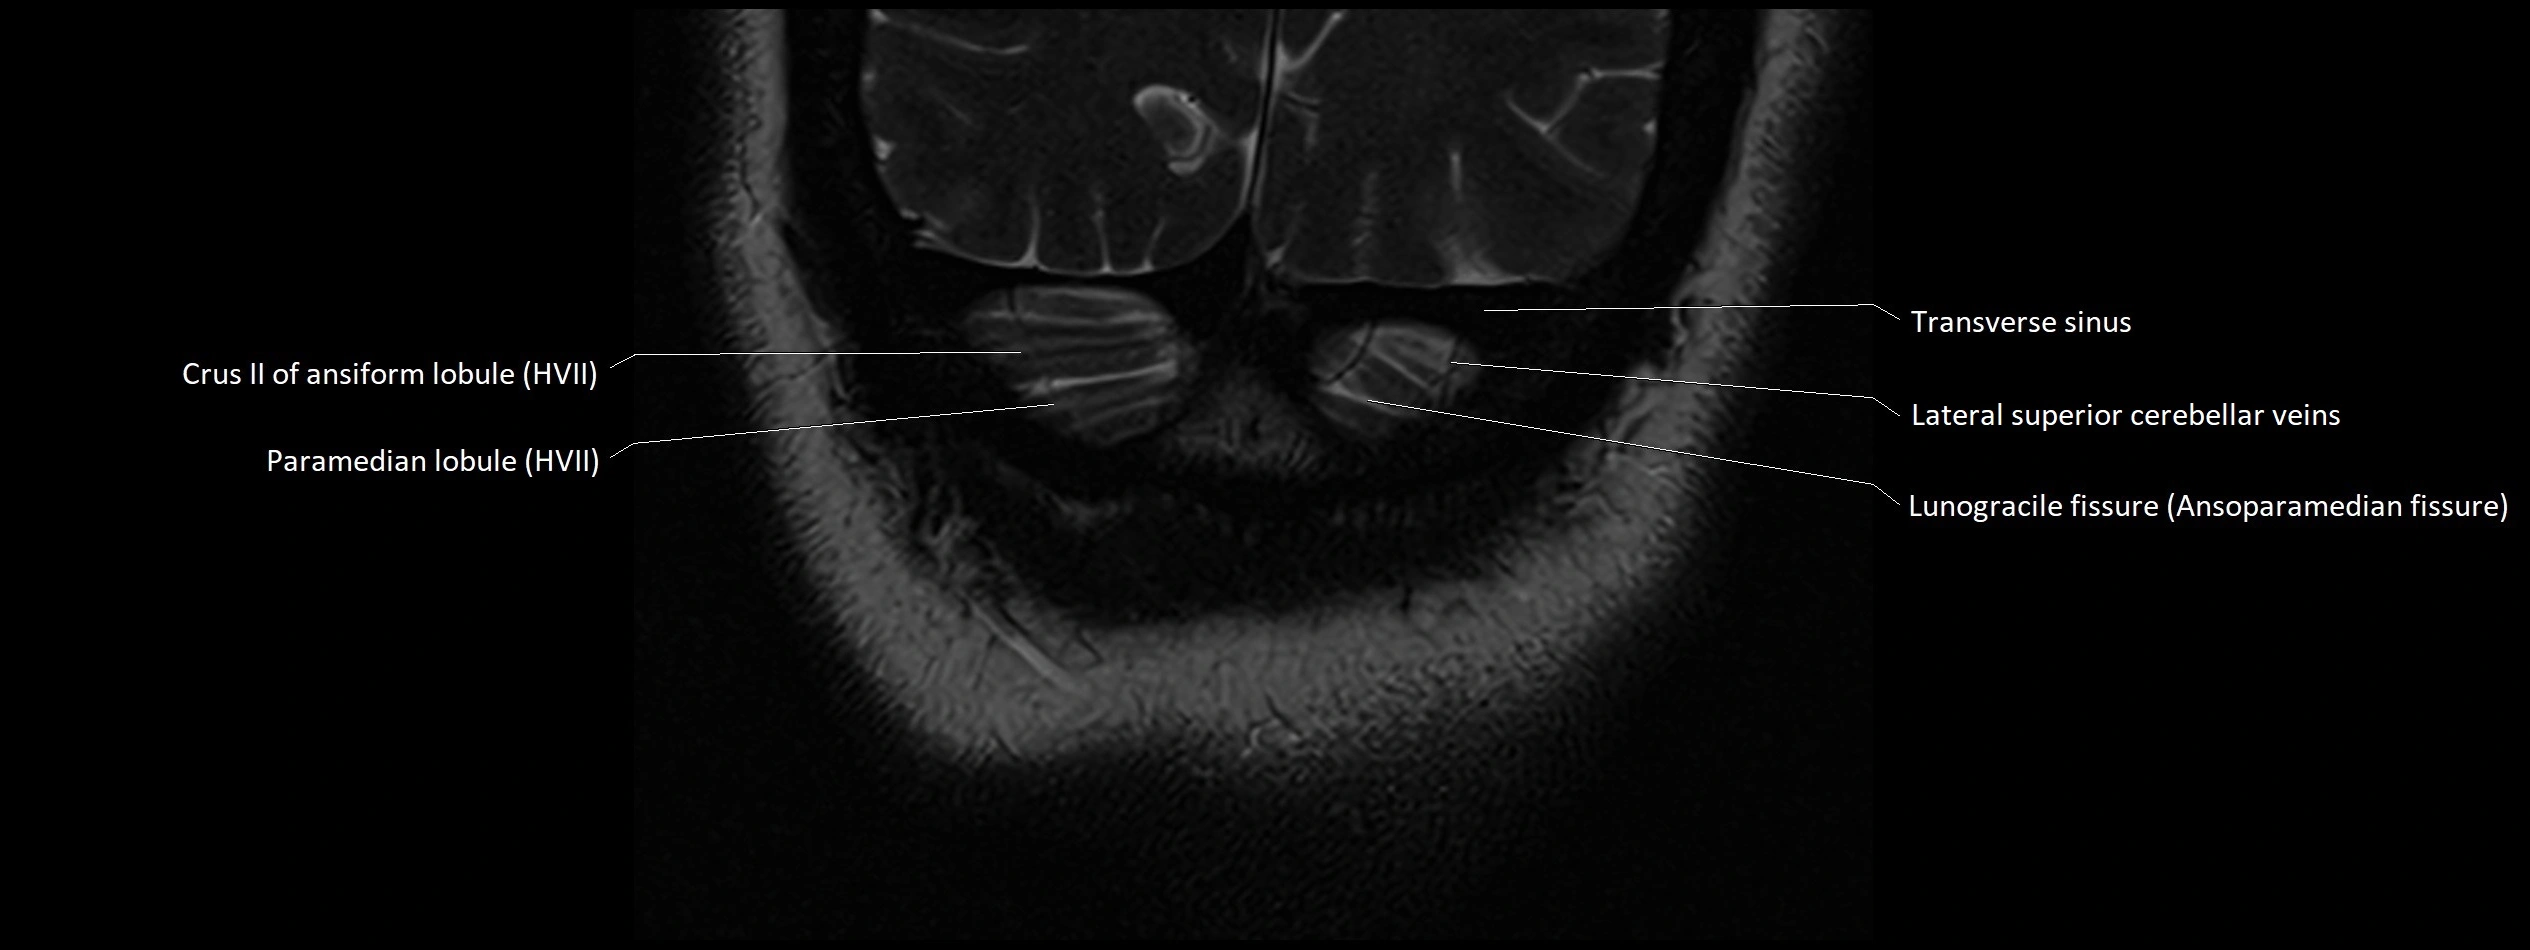

- Crus II of ansiform lobule of cerebellum

- Paramedian lobule (HVII) of cerebellum